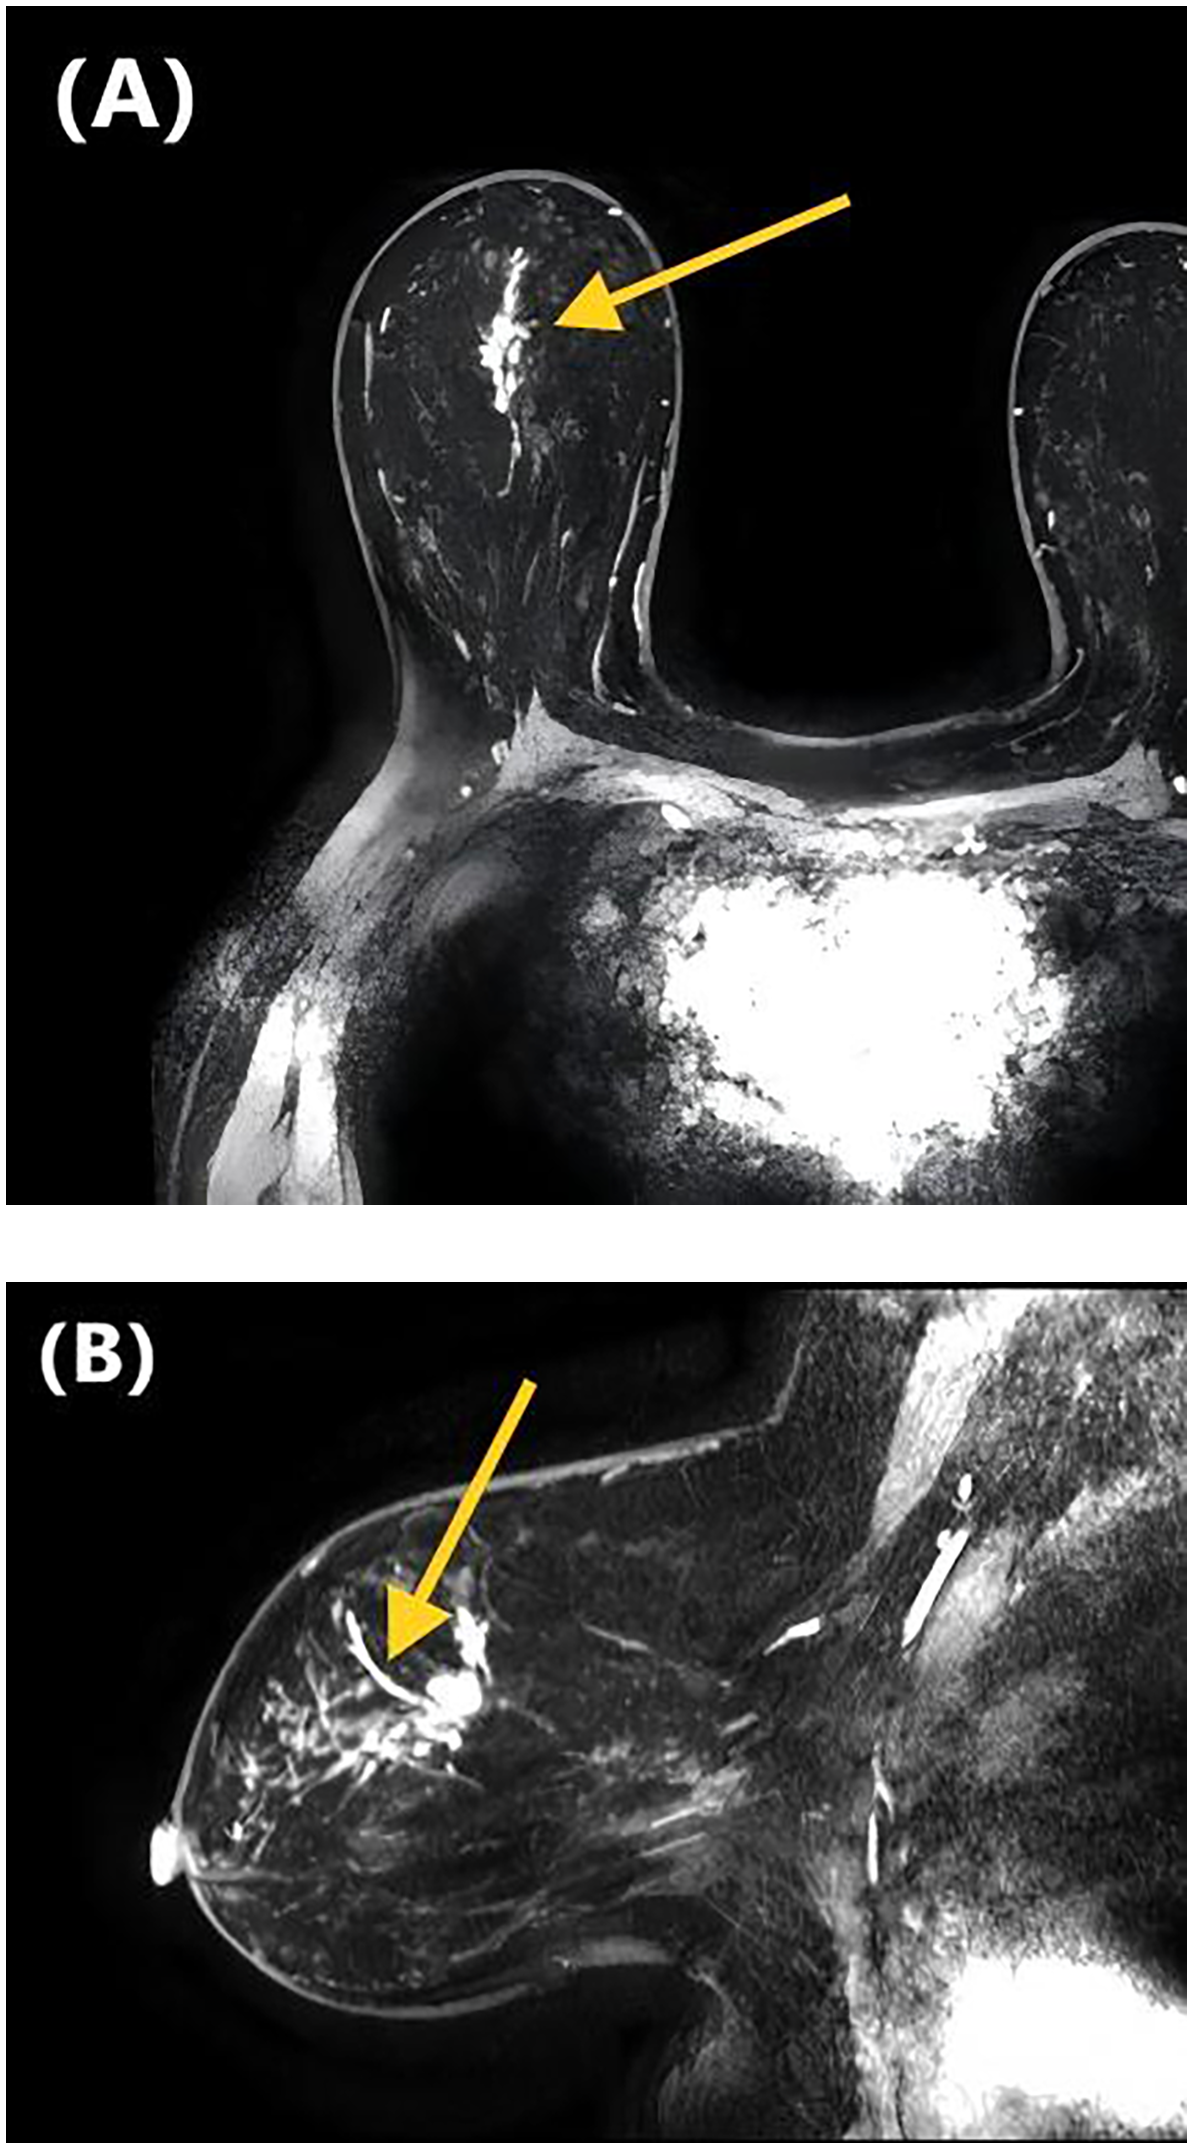

Table 2 presents the GVIF analysis used to assess multicollinearity. The regression model demonstrated an absence of significant multicollinearity, as all adjusted GVIF values were below 2.24 except for PR status. Although the GVIF for PR status exceeded 2.24, it remained below the 3.16 tolerance threshold, indicating acceptable collinearity levels. After controlling for confounding factors through multivariate logistic regression analysis, four risk factors associated with LVI formation were identified (Table 3). Patients aged ≥45 years (OR = 0.406, 95% CI: 0.191-0.844, P = 0.017) and those with higher ADC values (OR = 0.133, 95% CI: 0.017-0.825, P = 0.041) had a lower risk of LVI formation. Among the NME distribution patterns, patients with linear distribution had a significantly higher risk of LVI positivity compared to those with focal distribution (OR = 13.540, 95% CI: 1.390-172.644, P = 0.030) (Figures 1, 2), while no statistically significant differences were found for segmental, regional, multiple region, or diffuse enhancement patterns (all P > 0.05). Regarding molecular subtypes, compared to the Luminal A subtype, patients with Luminal B (OR = 5.081, 95% CI: 1.326-33.859, P = 0.039), HER2 overexpression (OR = 9.378, 95% CI: 1.922-71.460, P = 0.012), and triple-negative subtype (OR = 11.599, 95% CI: 2.043-96.710, P = 0.010) had a significantly higher risk of LVI formation.

Figure 1

DCE-MRI images of a 47-year-old woman with invasive ductal carcinoma of the right breast. Axial contrast-enhanced image (A) and sagittal contrast-enhanced image (B) show non-mass-like enhancement with the linear distribution. Lymphovascular invasion was confirmed at the histopathological examination.